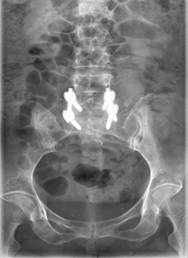

术后患者立即感到腰腿部不适明显缓解,术后24小时左右已在保护下站起,室内锻炼行走。术前症状几乎完全消失。术后复查X线片显示:腰5-骶1椎间隙高度较术前明显恢复,腰5椎体滑脱完全纠正,融合器位置理想。

术后复查腰椎正侧位